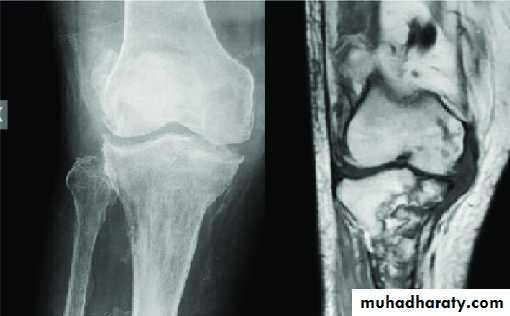

Imaging:

Pain x-ray:Priarticular osteoporosis,

Bone erosion and cystic lesion (on either sides of the joint) with little or no periosteal reaction, and

Progressive narrowing of joint space (phemister triad).

MRI: assess the extent of nerve tissue affection.